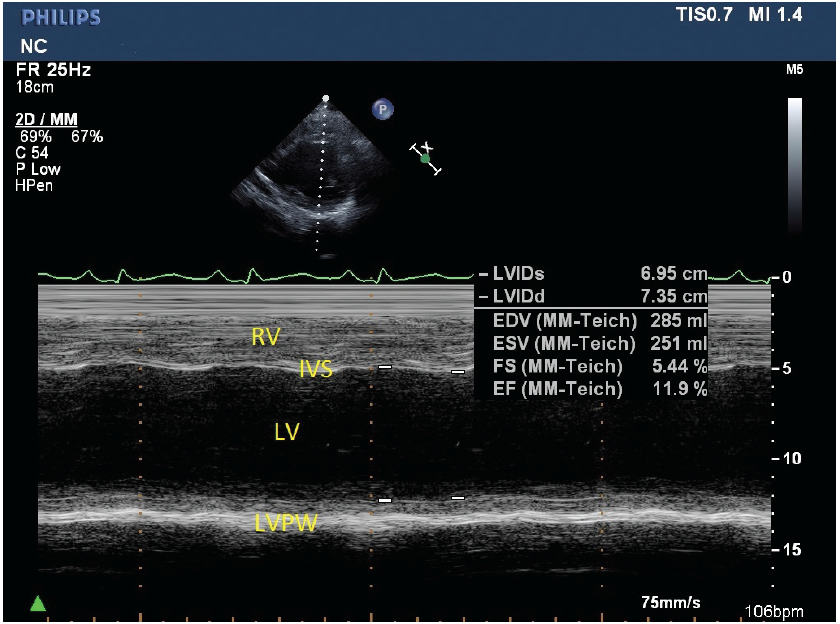

Roger Rossi, DO; Kathryn Eckert; Dawn Deike, DO; Chun Ho, MD

This article presents a case of severe DCM in a 15-year-old boy with DMD who presented clinically with gastrointestinal symptoms.